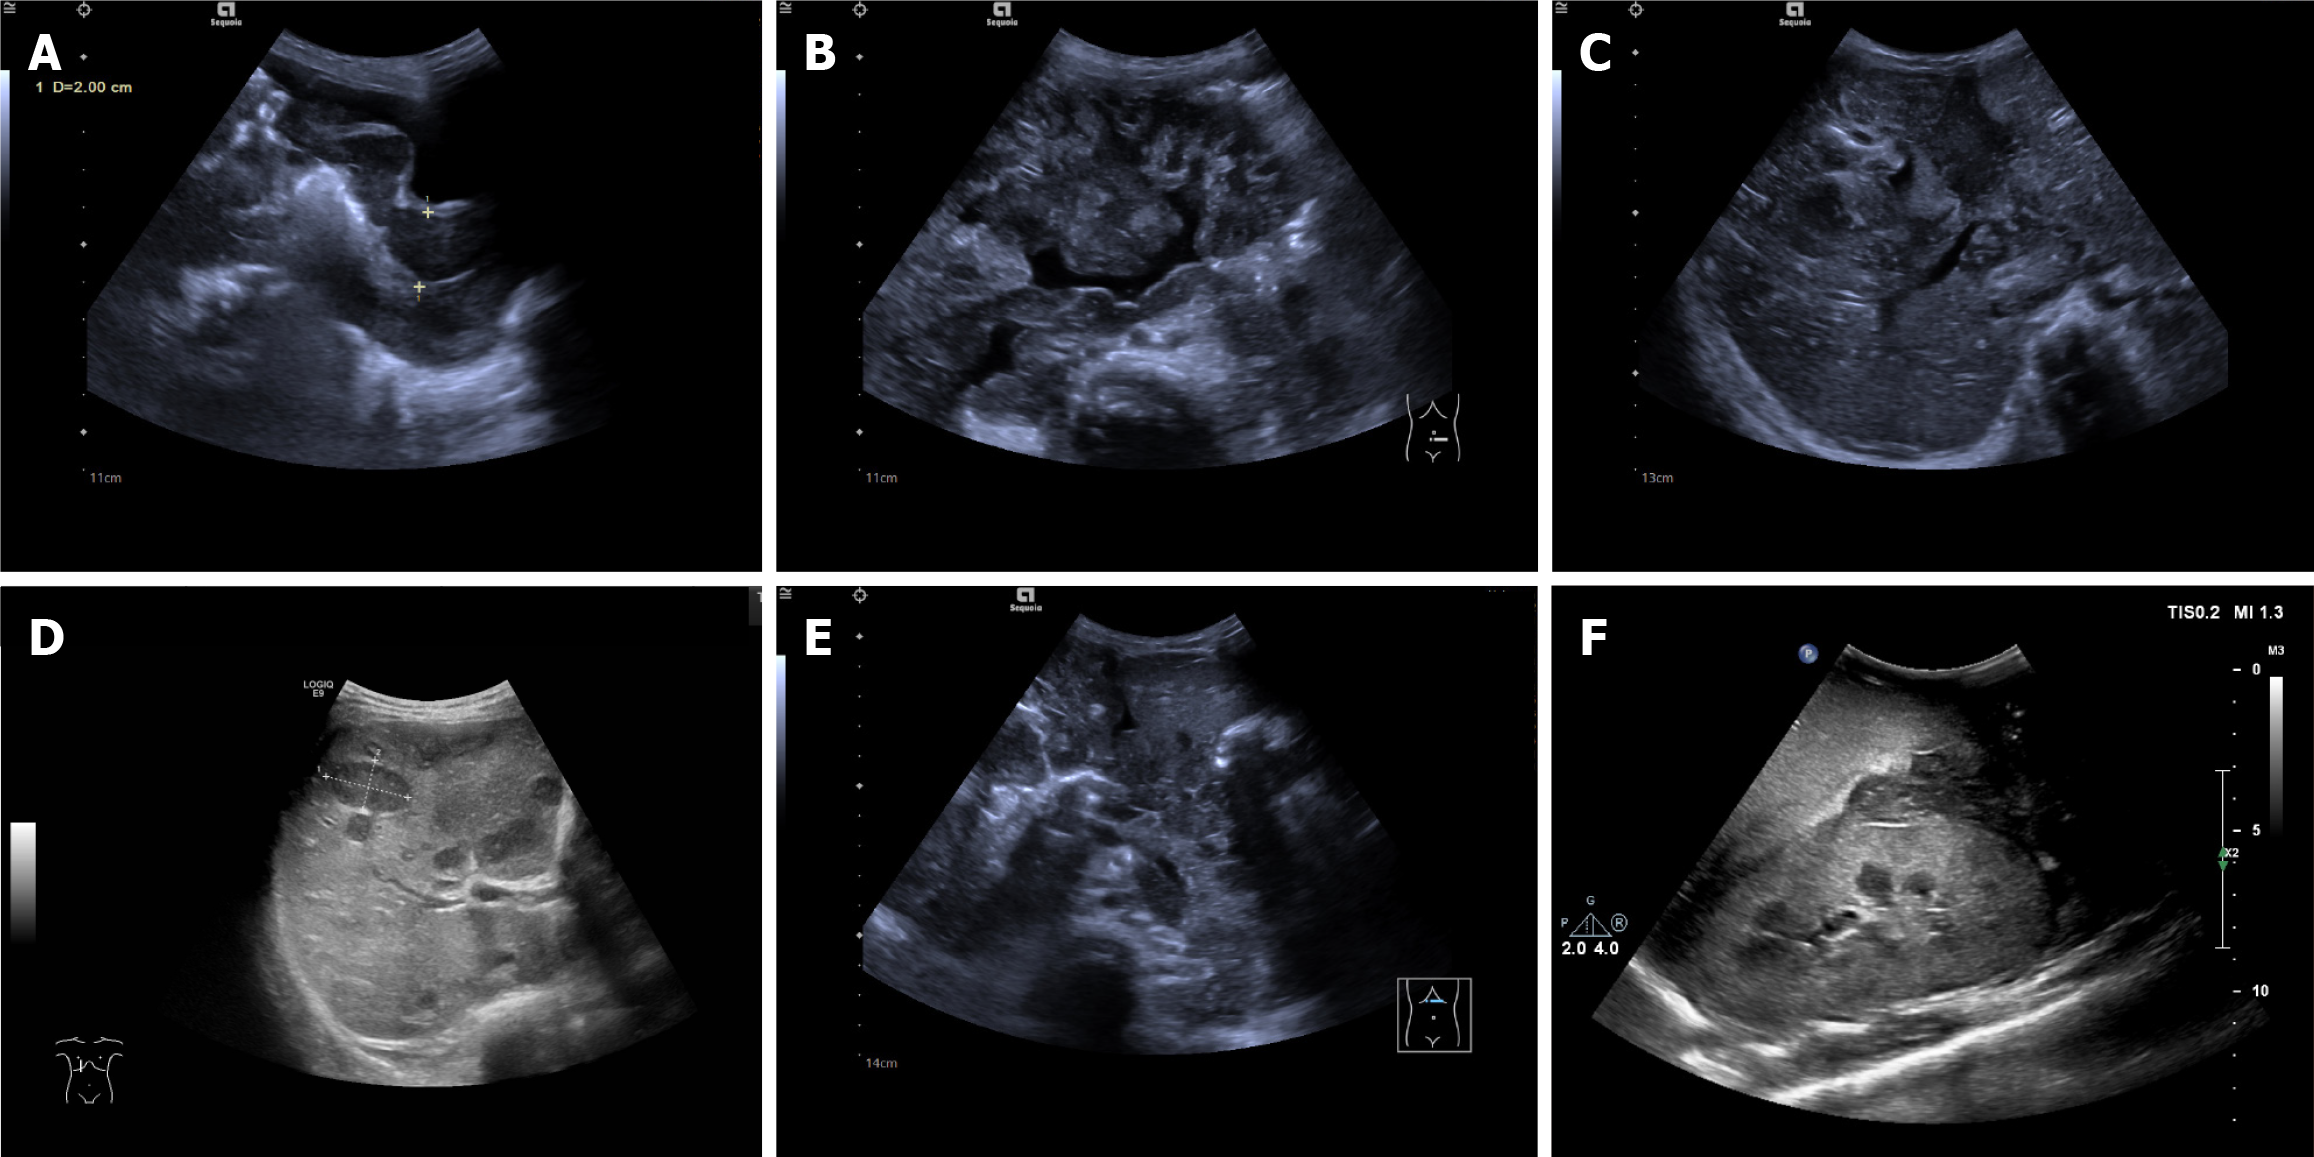

Figure 2 Changes in intestinal accessory structures in intestinal lymphoma.

A-C: Eccentric tumor-like thickening of the intestinal wall, eccentric intestinal mucosa (white arrow), and narrowed intestinal lumen, the mesentery was thickened and radially pulled the intestinal tract (yellow arrow), the adjacent adipose tissue was nodular (A and B), and the peritoneum was thickened and nodular (C); D: During the operation, tumor-like thickening of the intestinal wall and hyperplasia of the surrounding adipose tissue were observed.